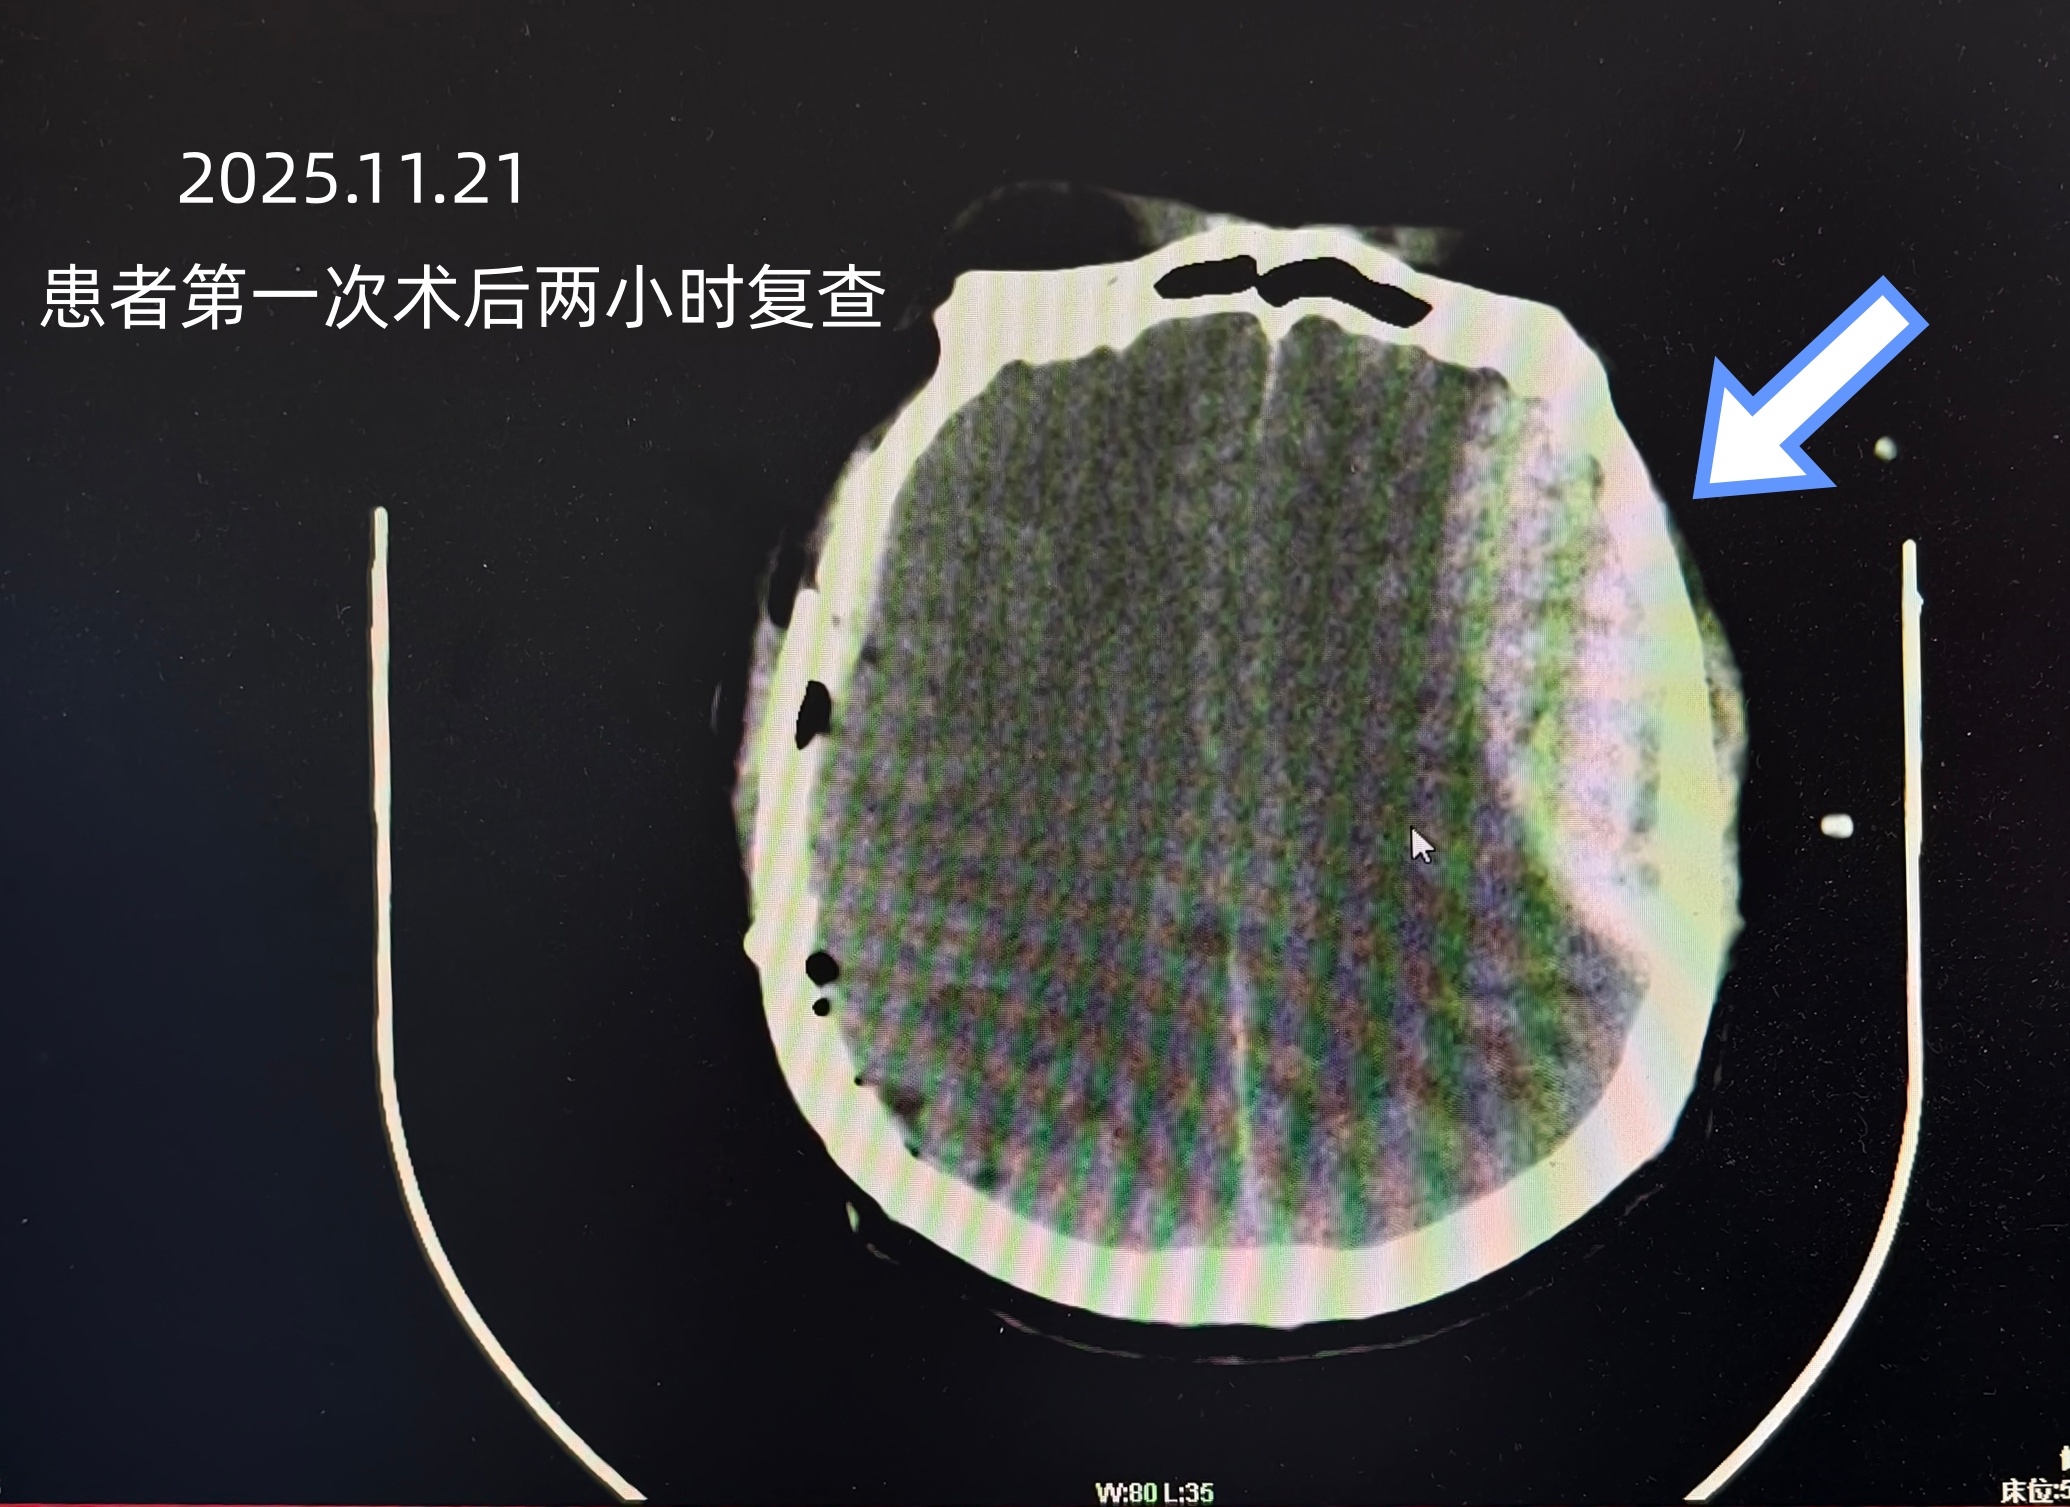

“常规情况下,血肿清除后患者意识应有所改善。他的‘不复苏’本身就是一个强烈的警示信号。”神经外科主任黄海涛介绍。面对异常情况,神经外科与重症医学科当机立断,在患者带呼吸机支持的情况下,经过多方协调调度,于术后两小时冒着风险将其转运进行影像复查。复查结果显示,患者对侧颅内出现迟发性出血。如果不是这次果断的复查,等患者出现明显症状时,大脑神经可能已遭受不可逆的损伤,结局将截然不同。